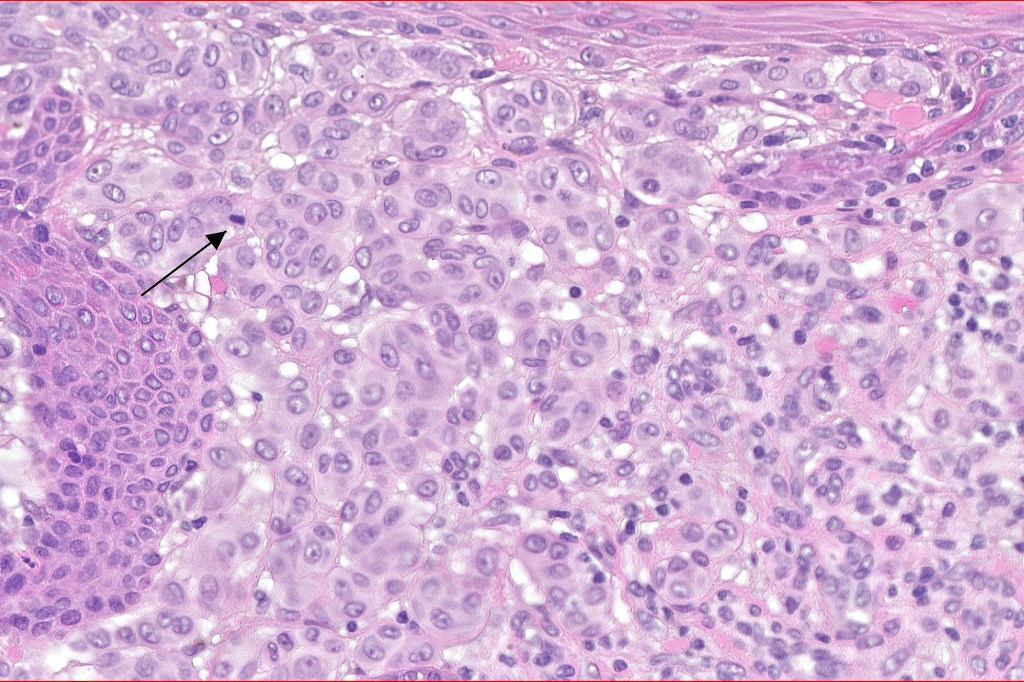

Histological features

•Large nodules which often show impaired maturation

•Loss of gradient with HMB45 and Ki67

•>20% Ki67 expression